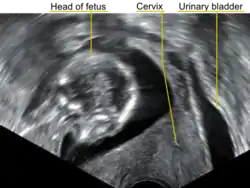

A transvaginal ultrasound showing a retroverted uterus during pregnancy. The cervix lies posteriorly to the urinary bladder, and the uterus normally extends superiorly from it, but the direction of the body of the fetus reveals that the uterus extends backwards.